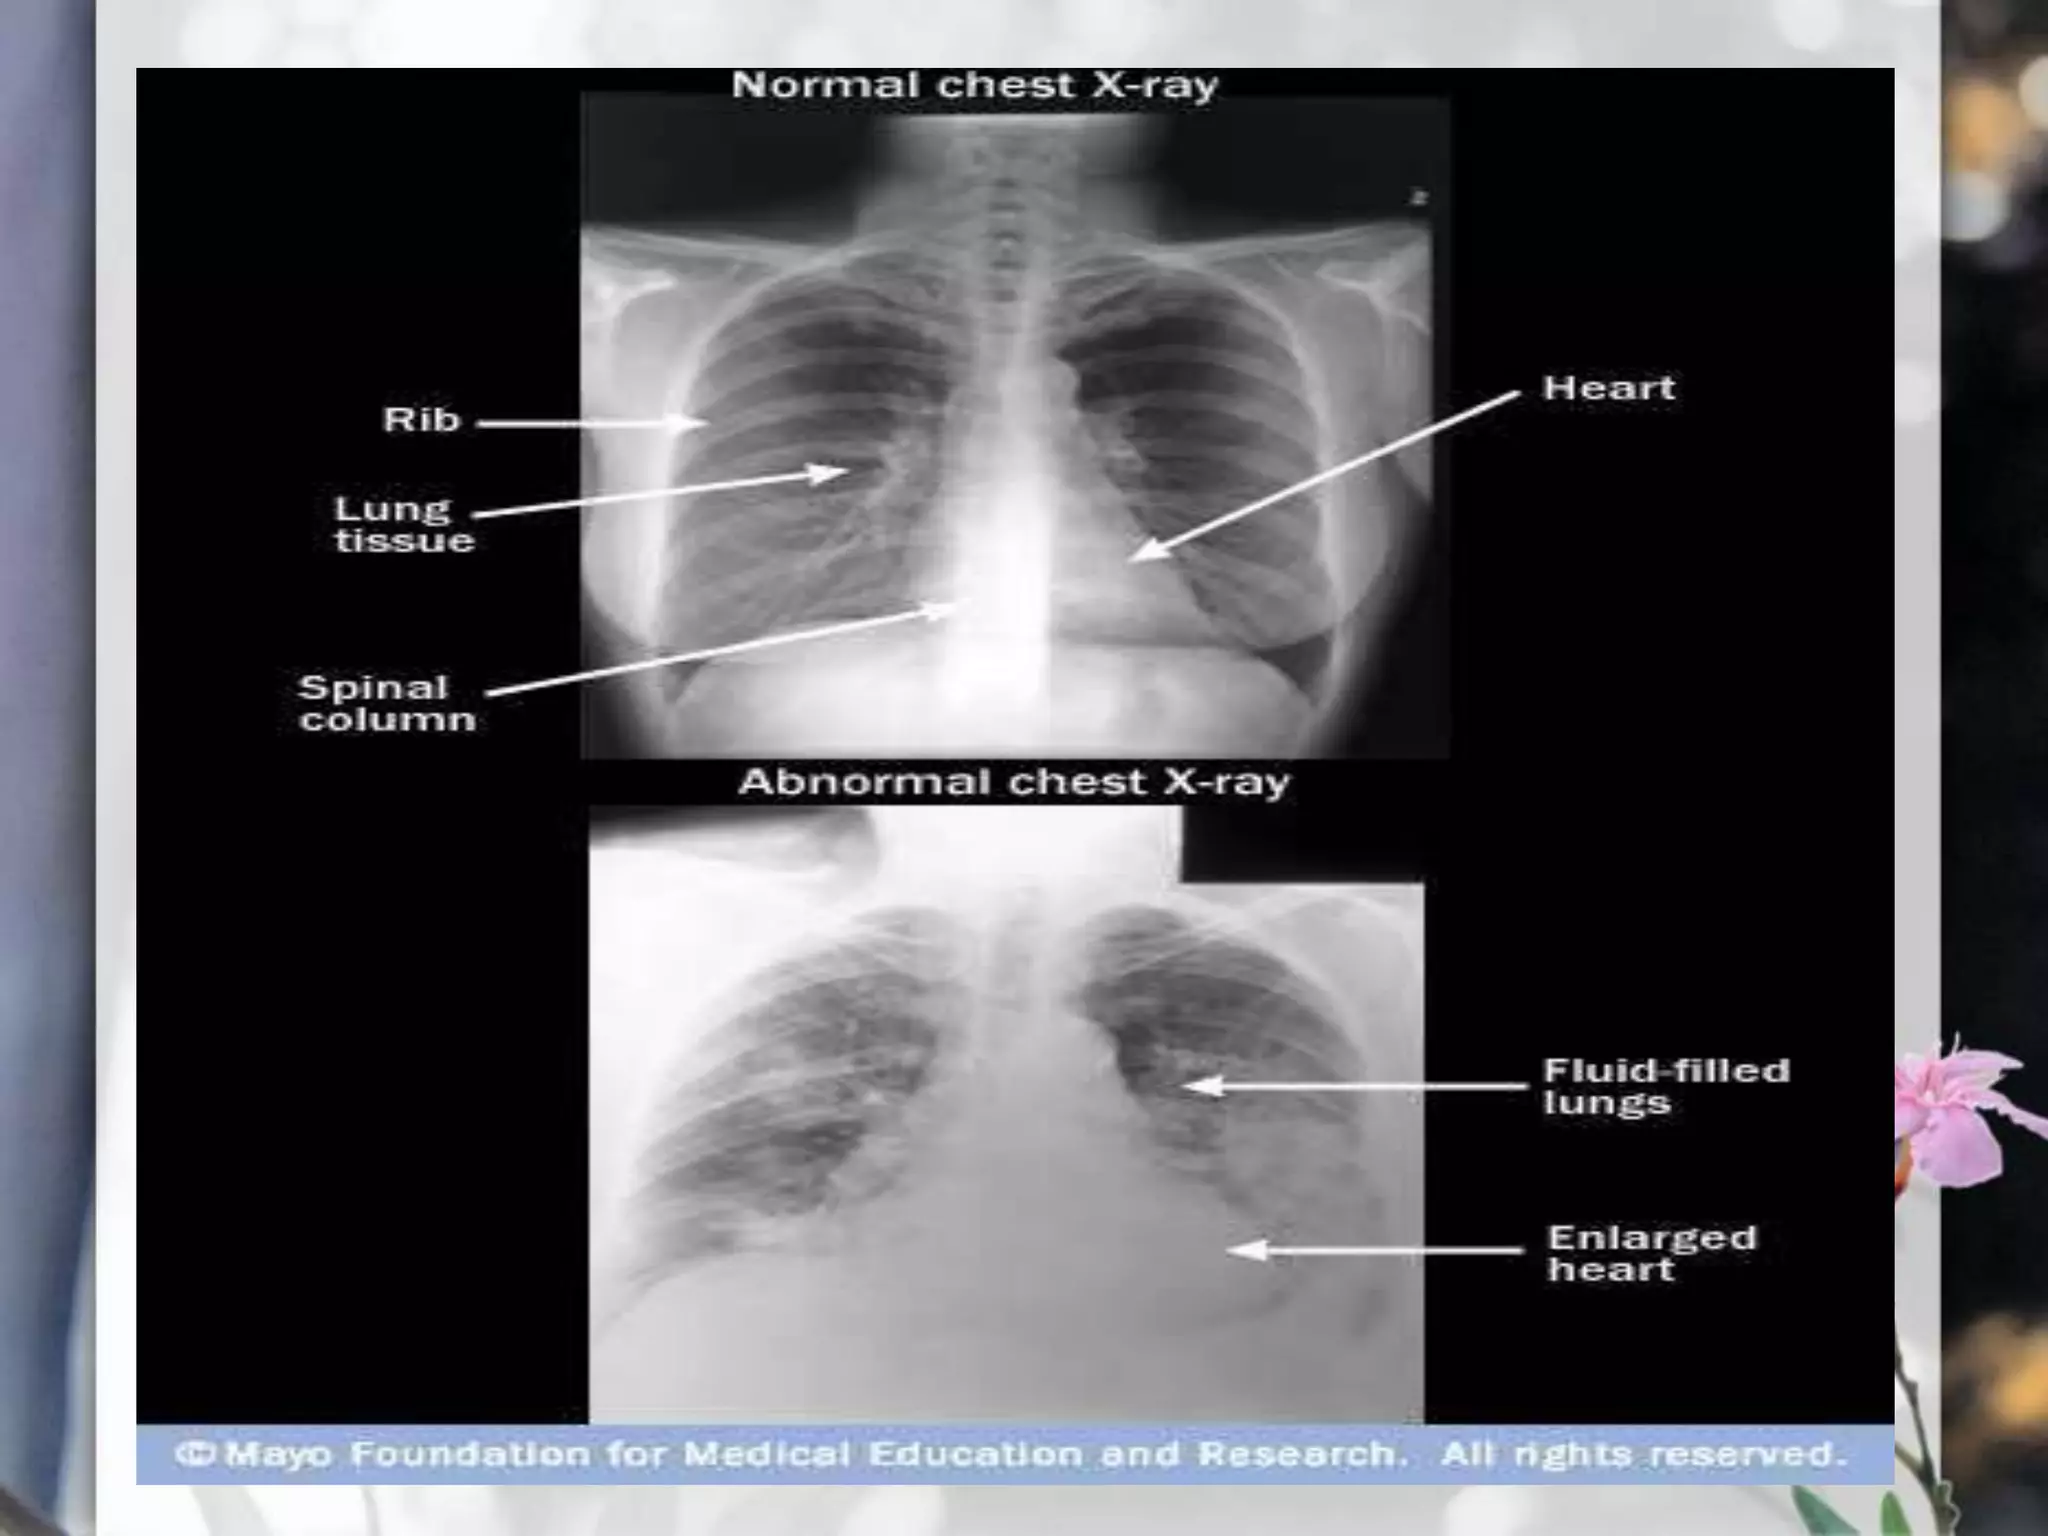

Chest X-RAY

•A radiology test that involves exposing the chest briefly to

radiation to produce an image of the chest and the internal

organs of the chest.